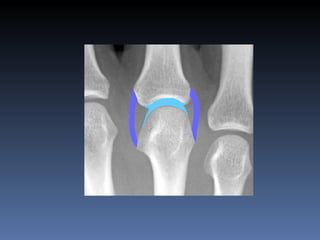

Artritis erosiva

erosiones